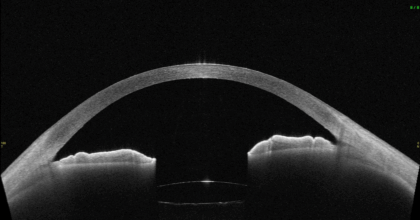

隅角が非常に狭く、眼圧が非常に上昇し緑内障発作となっている状態

白内障手術を行い、隅角が広がった状態

手術前後の画像を重ね合わせると、隅角が広がっていることがよくわかります